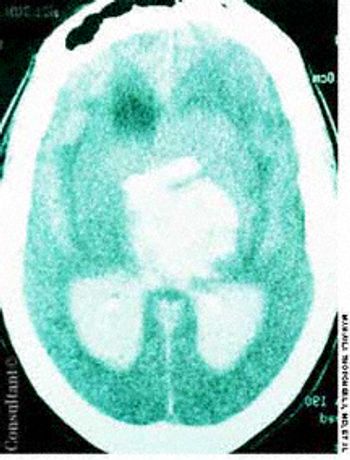

A 60-year-old comatose man was brought to the emergency department (ED). He had a history of diabetes, hypertension, and alcohol abuse. Relatives reported that the patient was noncompliant with his antihypertensive medication regimen.